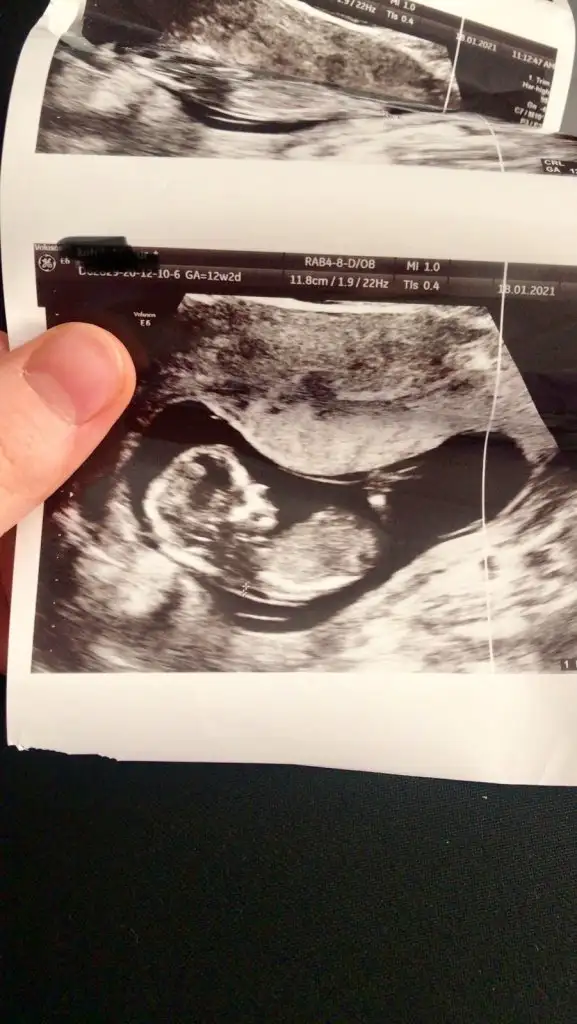

Erkek görünüyorAmin canım hepimizin12 haftalık usg resmi benimde

Bakalım bu hafta gidicem büyük ihtimal söyler heraldeErkek görünüyor

Net değil nubu emin olamadim başka USG varsa paylaşın sanki kız ama emin değilimMerhaba 12 haftalık tahmin edebilir misiniz

Eki Görüntüle 2764653 doktor da Kıza benzetti. Çizebilir misiniz rica etsem. Teşekkürler.